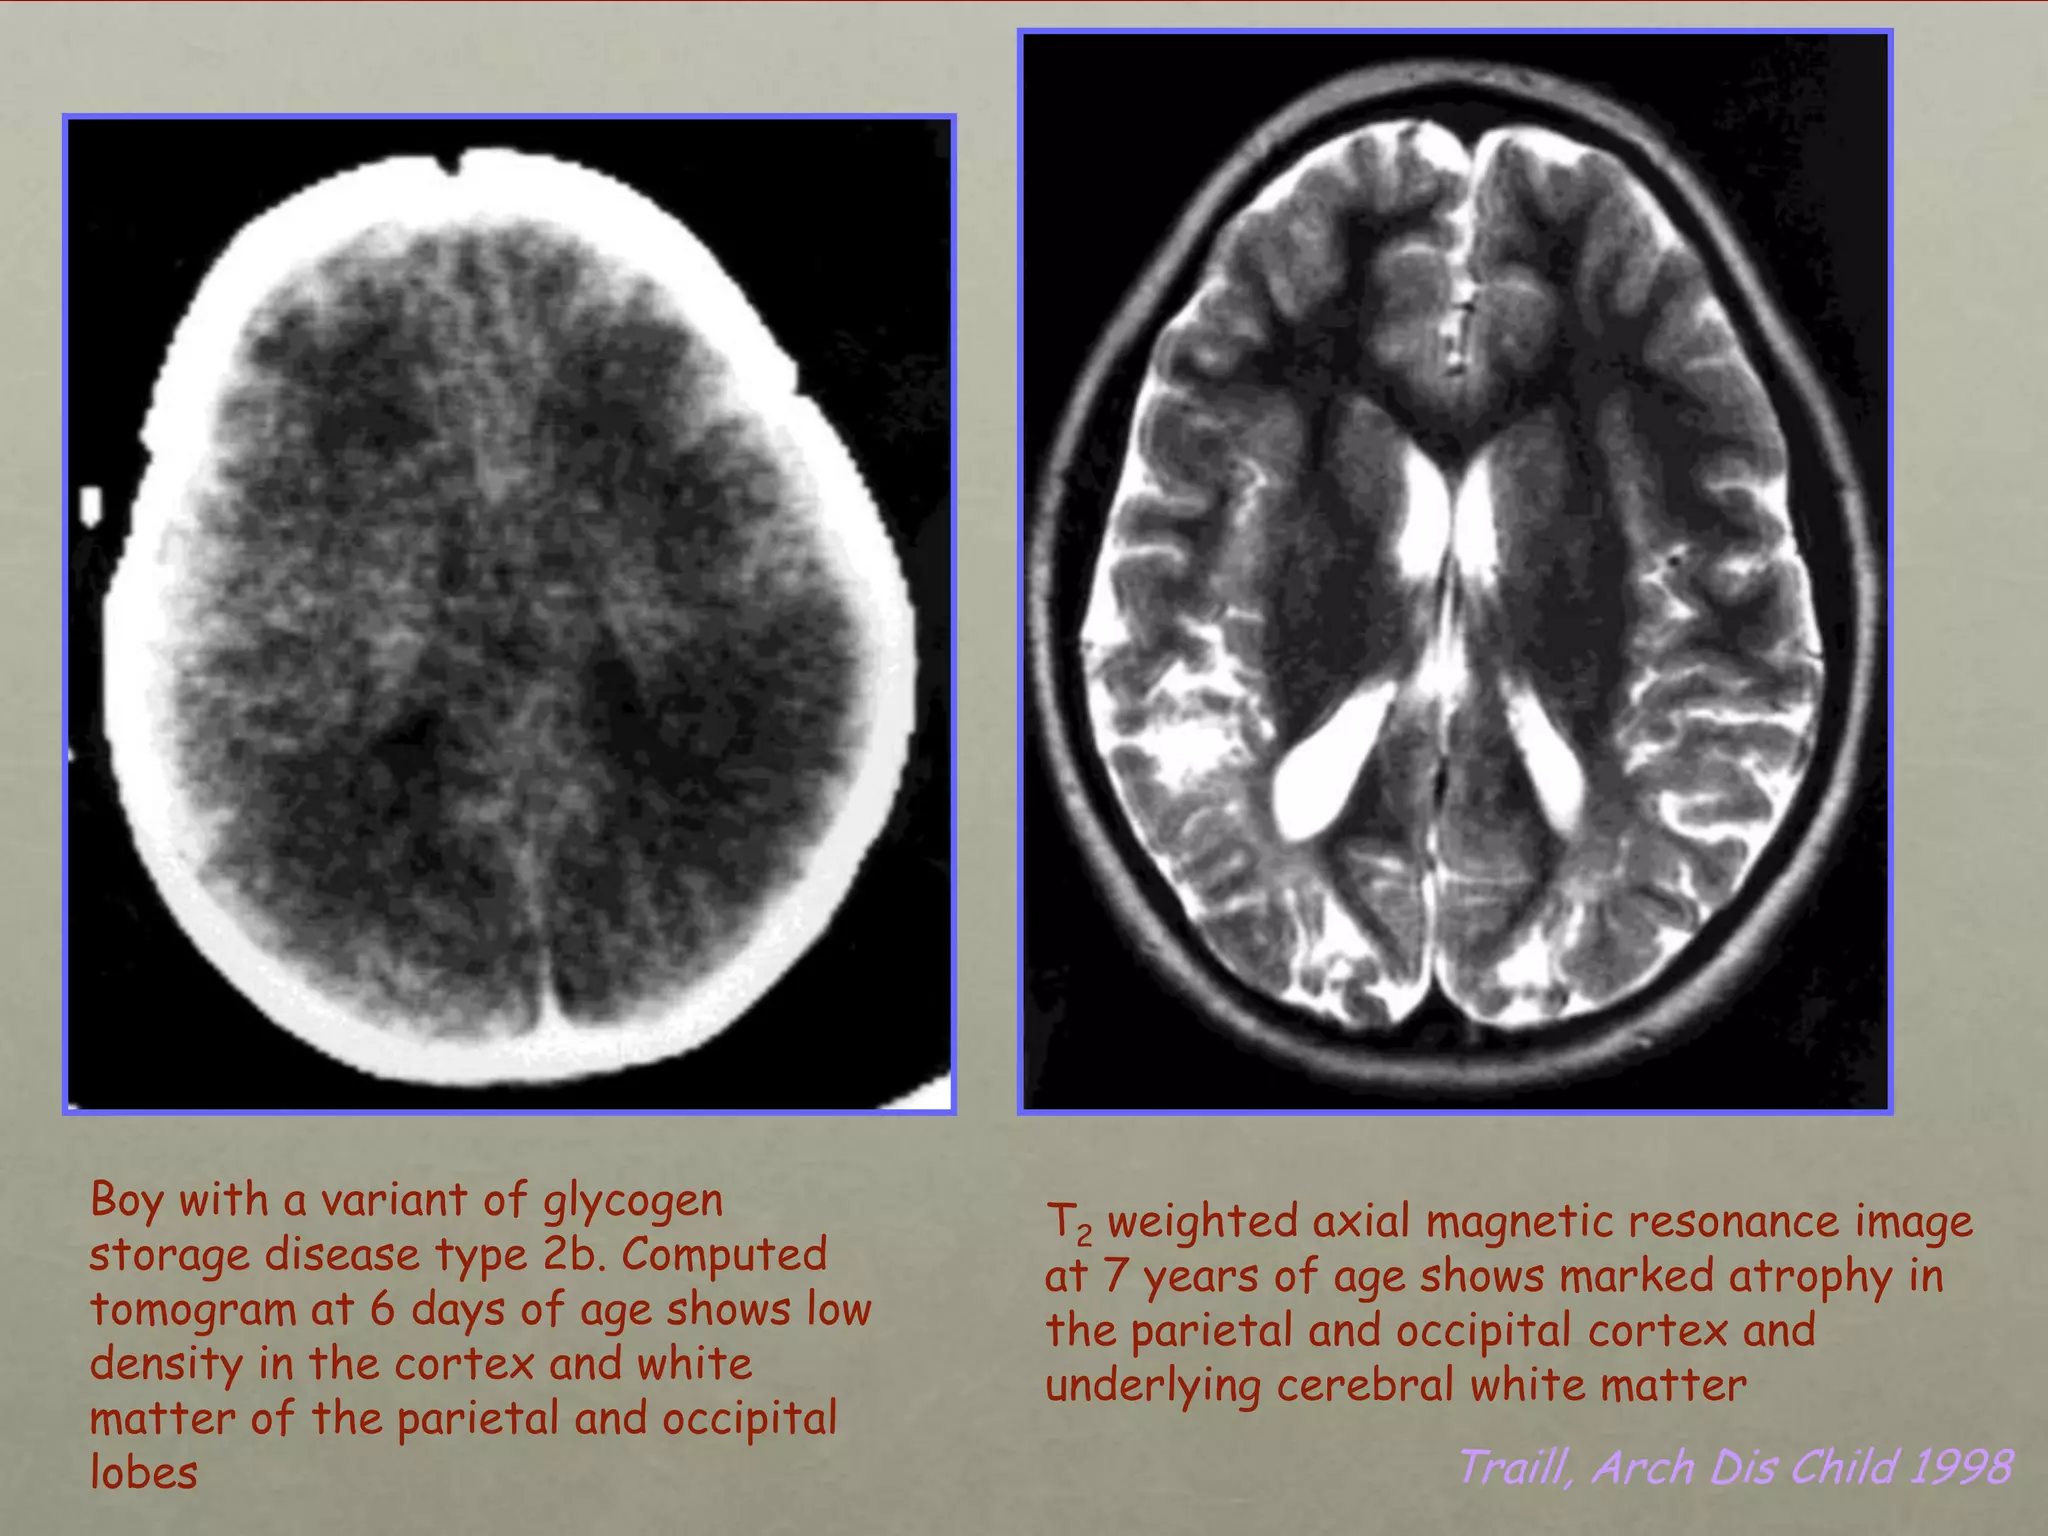

Boy with a variant of glycogen

storage disease type 2b. Computed

tomogram at 6 days of age shows low

density in the cortex and white

matter of the parietal and occipital

lobes

T2 weighted axial magnetic resonance image

at 7 years of age shows marked atrophy in

the parietal and occipital cortex and

underlying cerebral white matter

Traill, Arch Dis Child 1998

Boy with avariant of glycogen storage disease type 2b. Computed tomogram at 6 days of age shows low density in the cortex and white matter of the parietal and occipital lobes T2 weighted axial magnetic resonance image at 7 years of age shows marked atrophy in the parietal and occipital cortex and underlying cerebral white matter Traill, Arch Dis Child 1998